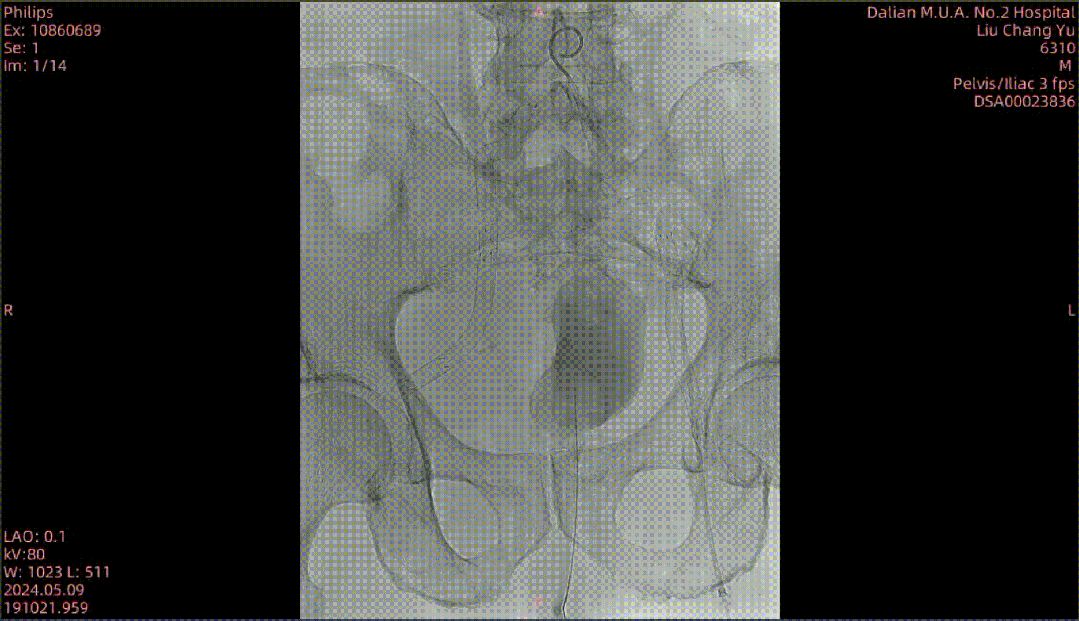

图为:腹主动脉造影,左髂动脉主干 不易 分辨

图为:0.018导丝配合pig导管+CXI支持导管翻山,真腔通过

图为:于左髂动脉分叉处依次置入cordis(10-8)接ev3(8-120)支架各1枚,球囊 轻度 后扩

图为:股浅动脉 待二期处理